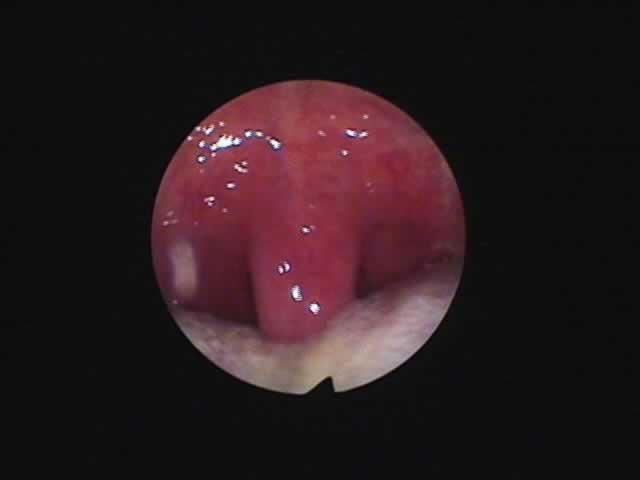

1) 手術前 37歳男性 2) 外来(日帰り手術)手術後45日、いびきはほとんど消失